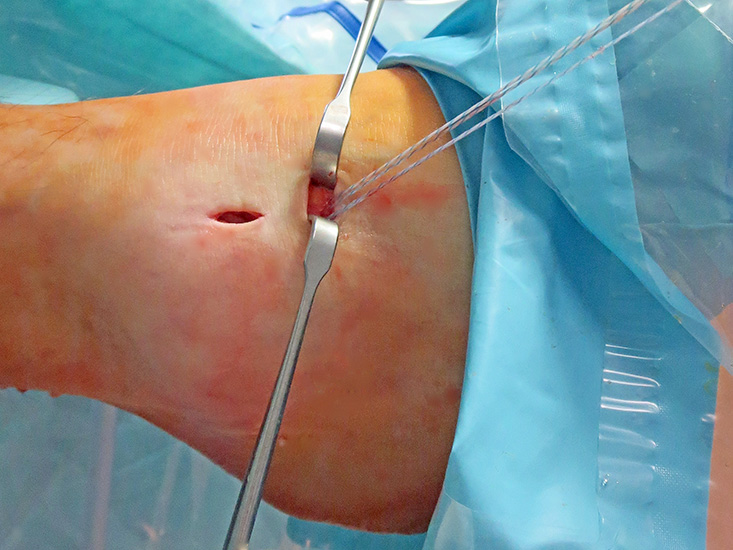

Operationstechnik

Nachfolgend wird die OP-Technik an einem rechten Sprunggelenk unter Verwendung von PEEK-Ankern veranschaulicht.

Video 1

Intra- und extraartikuläre Darstellung des Operationsablaufs am linken Sprunggelenk mit selbstschneidenden Titanfadenankern.